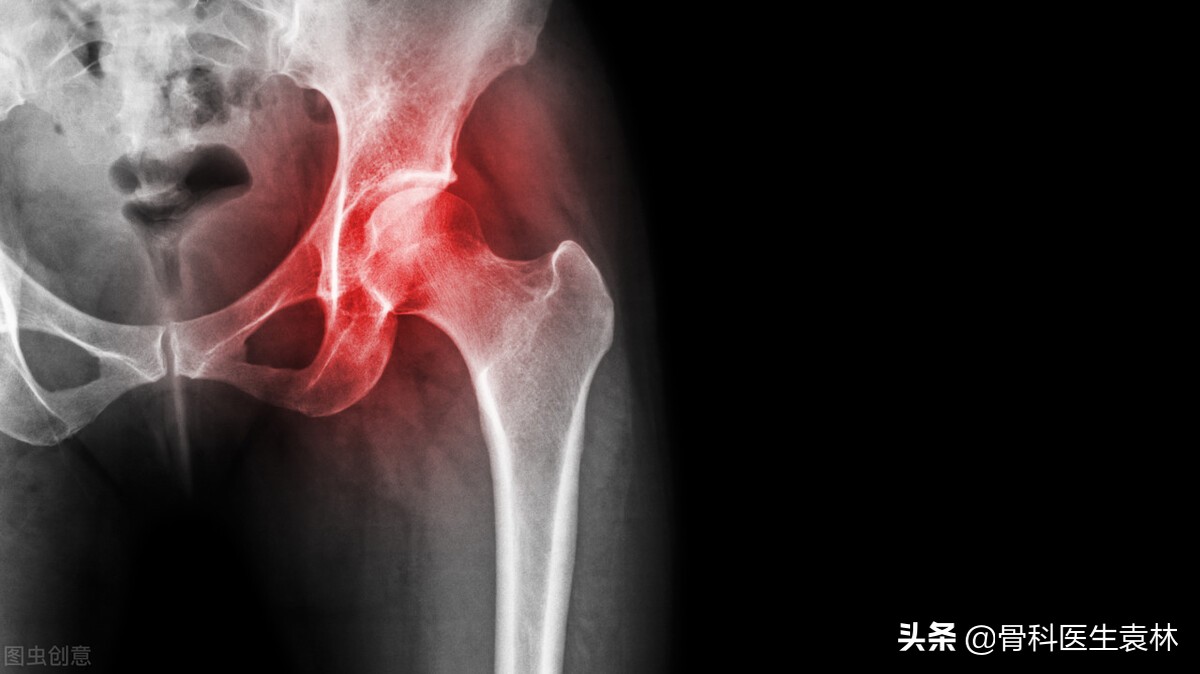

早期股骨头坏死怎么治疗?股骨头坏死早期怎么治疗?

股骨头坏死的主要病因是创伤,在日常生活中因为外力的撞击,造成了股骨颈骨折、髋关节扭挫伤、髋关节脱位的情况,导致股骨头因缺血而坏死。

患上股骨头坏死后,患者会有臀部、腹股沟酸疼、髋关节疼痛

在负重或者运动后这种症状会明显加重,如不妥善治疗的话,可导致髋关节功能障碍甚至终身残疾。

通过髋部X光片、同位素骨显像以及髋部的核磁共振等方式,来进一步确定是否为股骨头坏死。